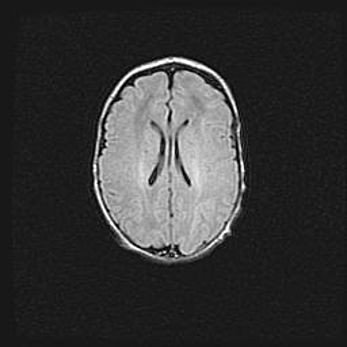

Сообщающаяся гидроцефалия. Кистозная энцефаломаляция головного мозга.

Возраст: 3 месяца 4 дня

Вес: 3100 г

Пол: женский

Окружность головы: 34 см

Срок гестации: 31 неделя

Кистозная энцефаломаляция головного мозга - одна из форм поражения головного мозга в детском возрасте. Характеризуется возникновением множественных и распространённых кист в коре, белом веществе и подкорковых образованиях головного мозга у плодов, новорождённых и детей раннего возраста. Развитие кистозной энцефаломаляции связано с внутриутробной асфиксией и гипотонией, родовой травмой, тромбозом синусов, пороками развития сосудов, инфекциями, сепсисом и другими причинами. Наиболее значимые инфекционные агенты: вирусы простого герпеса, цитомегалии, краснухи, токсоплазмы, энтеробактерии, золотистый стафилококк и другие.